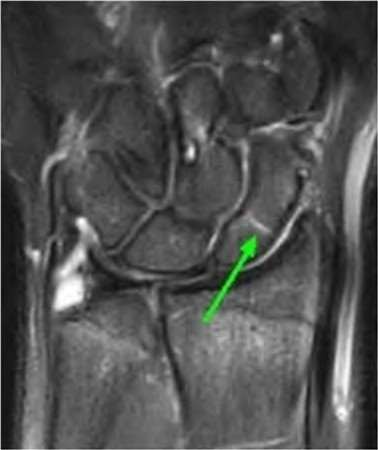

Question 6:

A 22-year-old male falls onto an outstretched hand and sustains a displaced fracture through the proximal pole of the scaphoid. Avascular necrosis of the proximal pole is highly likely due to the disruption of its primary vascular supply. Which vessel provides this critical retrograde perfusion?

Correct Answer: Dorsal carpal branch of the radial artery

Explanation:

The primary blood supply to the scaphoid is from the dorsal carpal branch of the radial artery, which enters the dorsal ridge of the scaphoid at the waist and courses proximally. This retrograde blood flow makes proximal pole fractures highly susceptible to avascular necrosis and nonunion. The superficial palmar branch provides a minor supply (about 20%) to the distal pole.